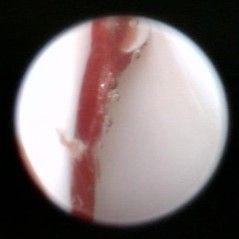

Arthroskopie

Ein minimal-invasiver Eingriff, bei dem mit Hilfe eines Endoskops die Einsicht in ein Gelenk ermöglicht wird.